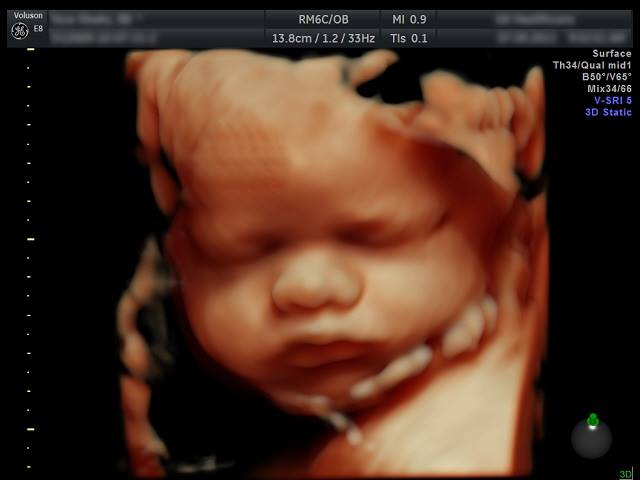

Dal 2004 frequenta il reparto di ginecologia ed ostetricia dell’ ospedale buccheri la ferla “fatebenefratelli” di palermo acquisendo le tecniche di ecografia ostetrica di i e ii livello, ecocardiografia fetale, screening per malattie cromosomiche fetali, diagnosi prenatale invasiva, parto indolore, gravidanza a rischio e pretermine, tecniche chirurgiche ostetriche e ginecologiche, isteroscopia, incontinenza urinaria.

Nel 2006 si abilita come operatore per ultrascreen (screening combinato di i e ii trimestre per malattie cromosomiche fetali) con la fetal medicine foundation di londra.